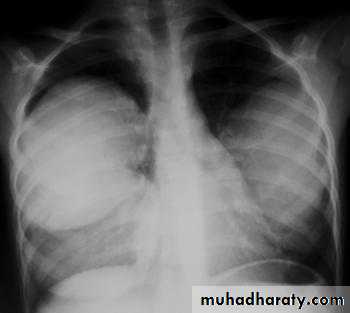

Pleural effusionX-ray of pleural effusion

Massive right effusion